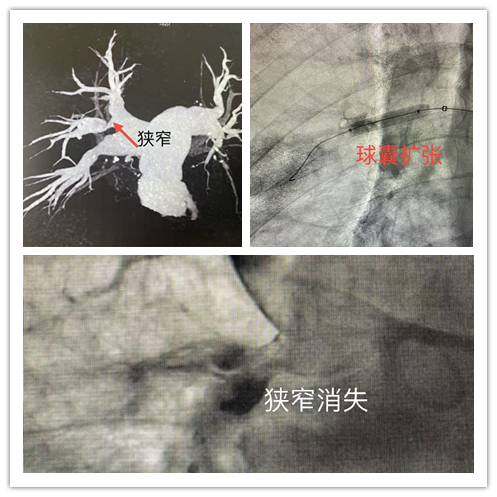

为改善郑嗲嗲的生活质量,介入三病区医护团队为郑嗲嗲实施了肺动脉造影+测压+肺动脉腔内成型介入治疗,凭借精湛的医术和先进的设备,精准地对病变血管进行处理。术后,患者肺动脉压力从76cmH2O下降到60cmH2O,下降了21%。目前,患者恢复良好,已顺利出院。

“如果把心脏比喻成泵,抽调全身血液,那么肺就是一个输氧机,在血液调度的过程中进行氧气补给。当输氧机的零部件出现问题,泵就会超负荷运转,并逐渐衰竭。”捷克论坛 马王堆院区介入血管外科三病区主任颜鹏介绍,肺动脉高压的介入治疗是一种重要的治疗手段。经皮肺动脉球囊成形术(BPA)是一种微创血管介入技术,其基本原理是先利用导管造影对肺动脉狭窄或闭塞病变进行定位,然后通过使用球囊对狭窄局部进行扩张,开通狭窄或阻塞血管,改善肺血流灌注,降低右心室后负荷, 达到治疗目的。